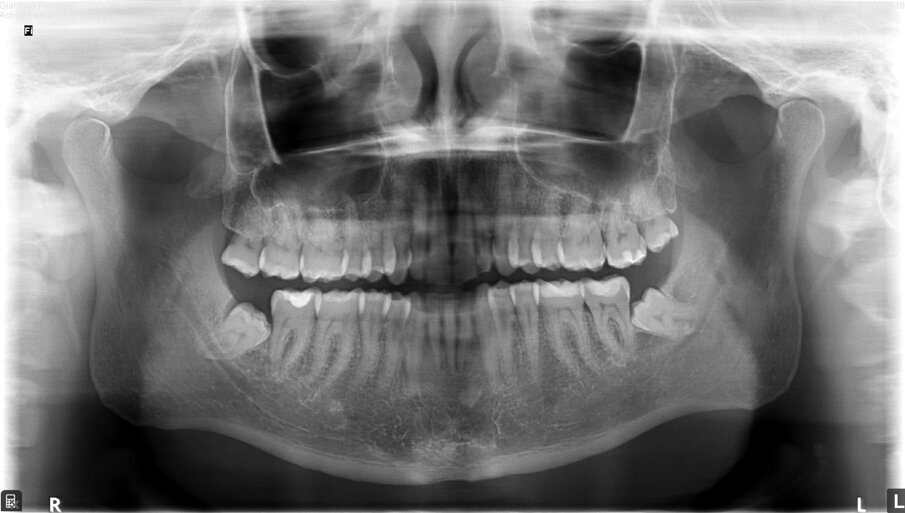

Diagnosi ed eziologia Un uomo sano di 39 anni si è presentato nel nostro studio ortodontico lamentando un aspetto dentale poco attraente e la paura della chirurgia ortognatica proposta da un altro ortodontista. Clinicamente, il profilo del paziente era rettilineo e la vista frontale non mostrava alcuna asimmetria facciale. L’esame funzionale non ha rivelato alcuna deviazione mandibolare o riduzione dei movimenti. Il paziente non aveva dolori articolari e non sono stati rilevati rumori articolari. Era presente una lieve occlusione molare bilaterale di Classe II, un morso aperto e un grave affollamento in entrambe le arcate. L’affollamento era particolarmente grave nell’arcata mandibolare, sebbene mancasse l’incisivo centrale mandibolare destro. Gli incisivi mascellari erano di piccole dimensioni, suggerendo una discrepanza dell’indice di Bolton se fossero stati presenti tutti e quattro gli incisivi mandibolari. Erano inoltre presenti un morso incrociato nella regione dell’incisivo laterale superiore sinistro e una grave rotazione distale del secondo premolare mandibolare sinistro (Figg. 1-8).

Figg. 1-8_Fotografie facciali e intraorali pre-trattamento.

Dal punto di vista parodontale il paziente ha mostrato una buona attitudine all’igiene orale, ma l’affollamento degli incisivi mandibolari ha reso difficile la pulizia in quell’area, causando un accumulo di placca e un’infiammazione gengivale localizzata. La radiografia panoramica ha rivelato la presenza dei terzi molari mandibolari e ha confermato l’assenza dell’incisivo centrale mandibolare destro (Fig. 10). L’analisi cefalometrica ha evidenziato una malocclusione scheletrica di Classe II (convessità del Punto A: 4,9 mm), una posizione leggermente retrusa del mento (profondità facciale: 78,1°) e una tendenza scheletrica al morso aperto (altezza facciale inferiore: 53,19°; asse facciale: 80,58°; Fig. 9). Gli incisivi mandibolari erano inclinati lingualmente (Li-APog: 9,3°) e retrusi (Li-APog: 1,55 mm), con un angolo interincisivo aumentato di 142,9°.